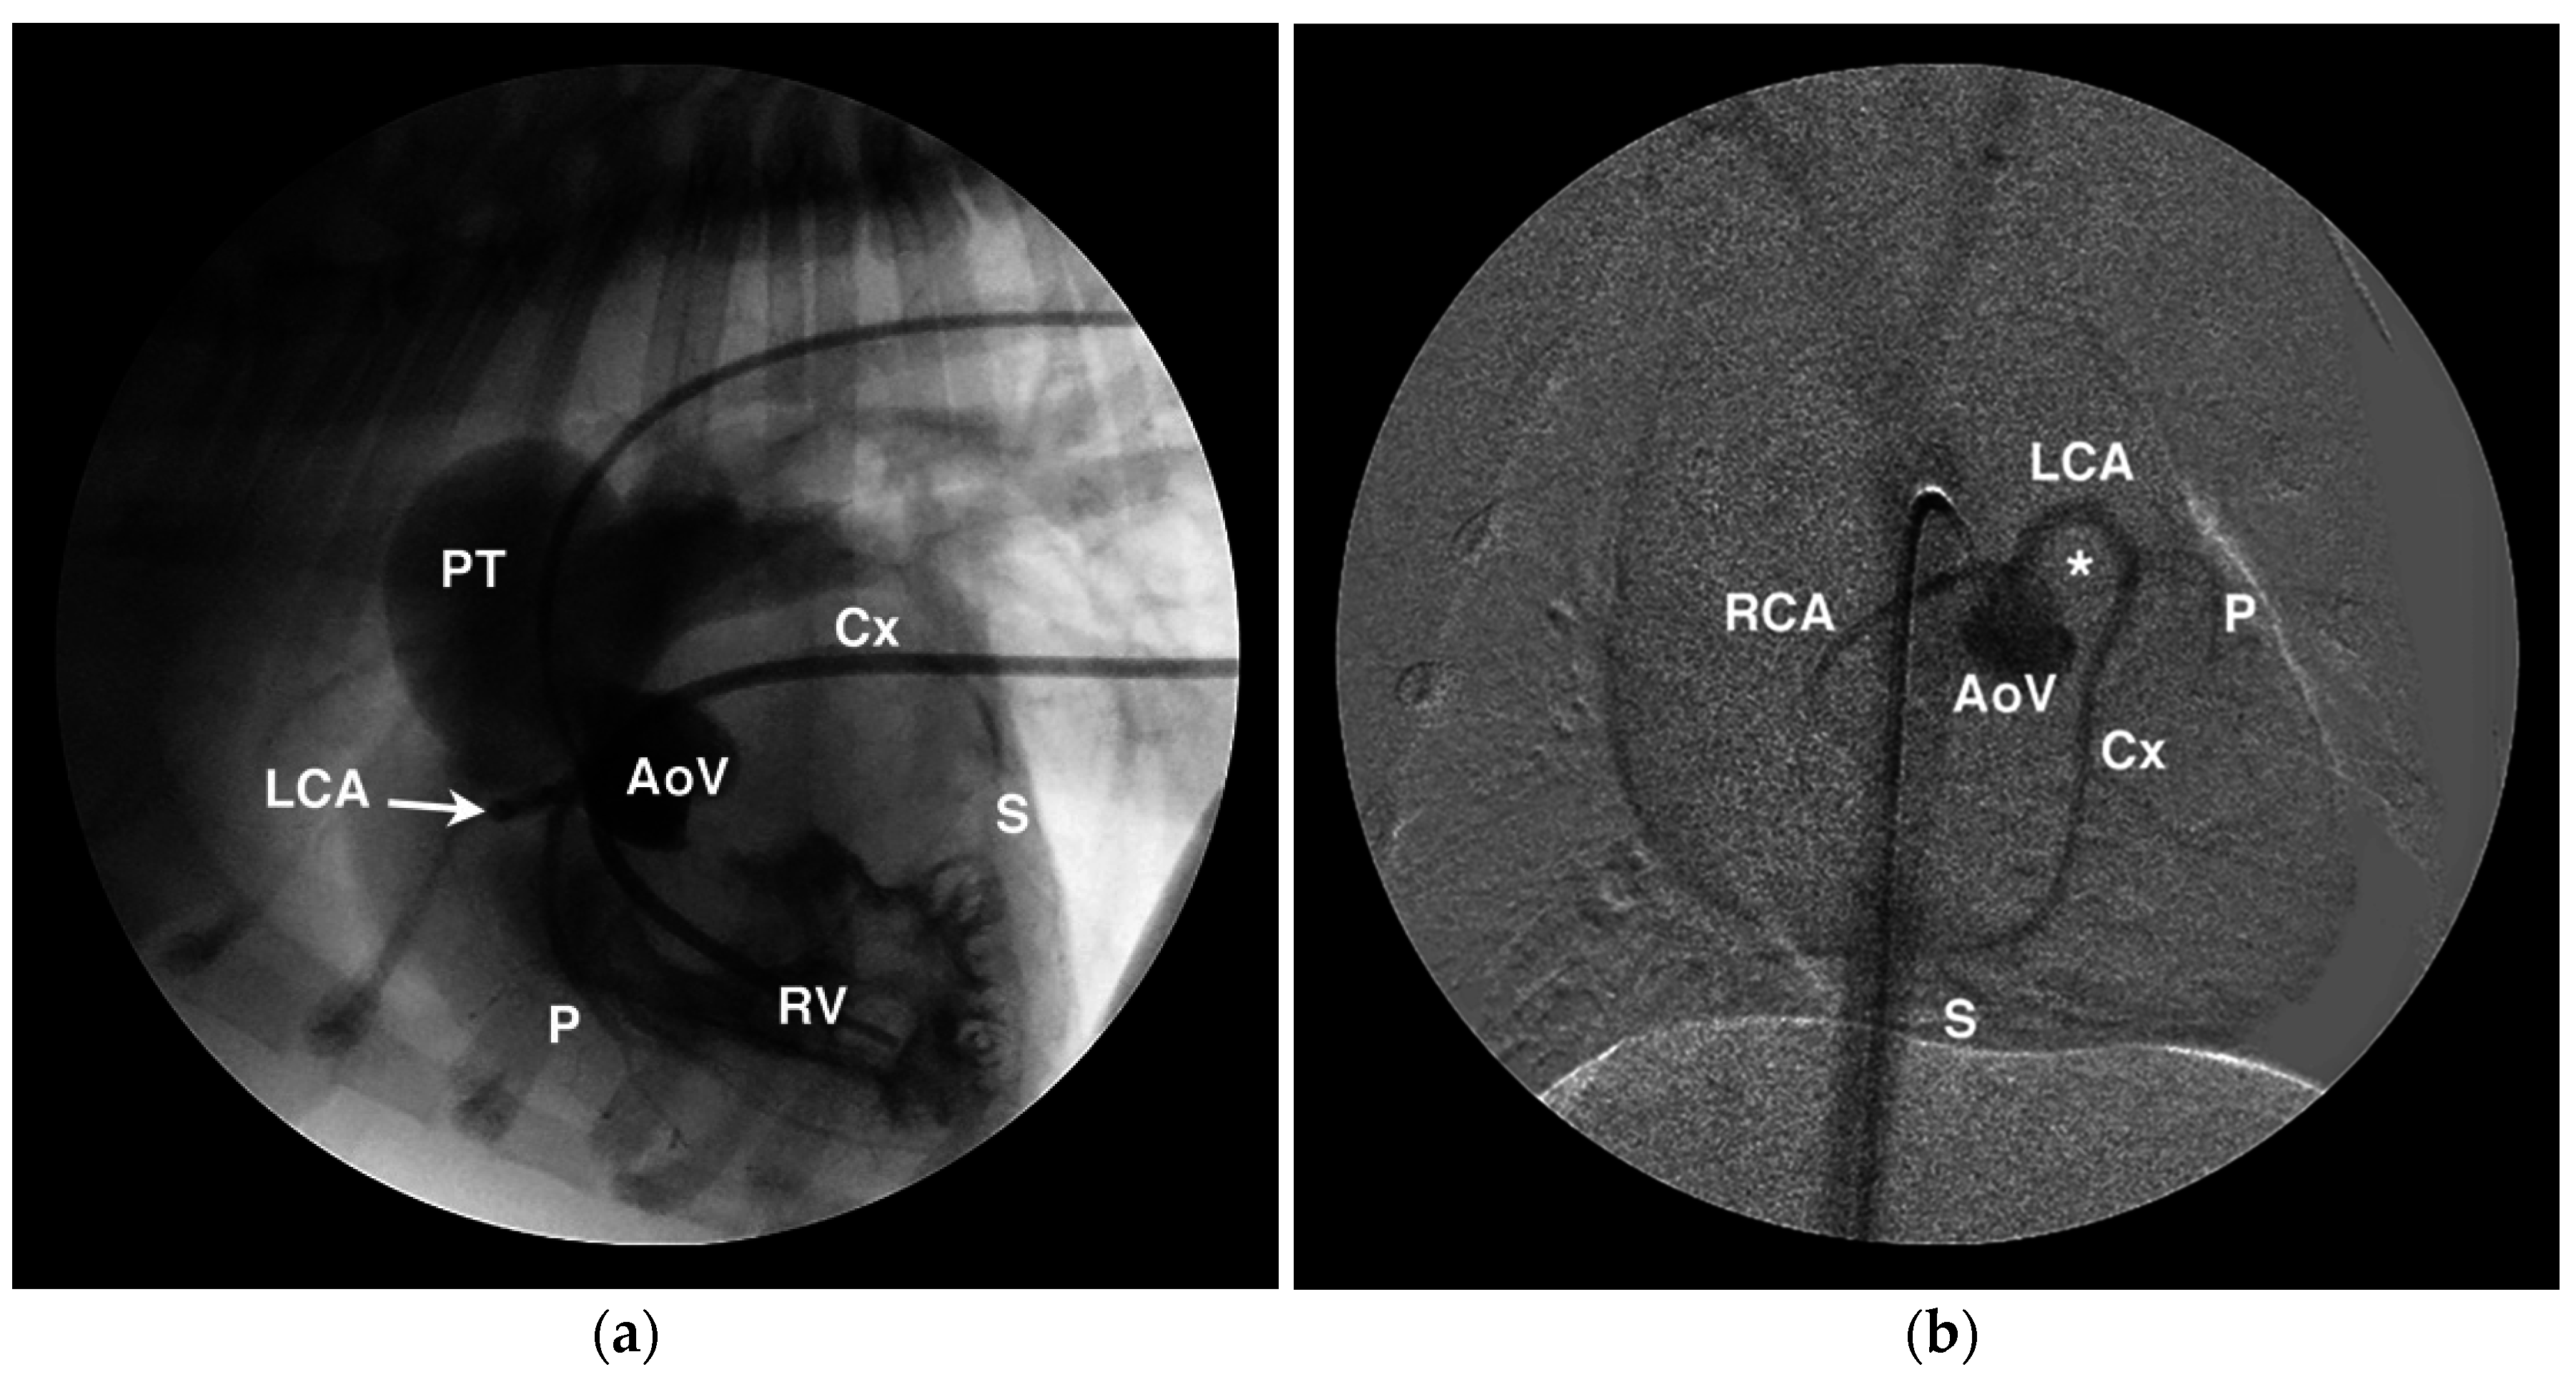

Figure 7.

Angiographic examples of anomalous coronary artery origin and course. (a) Lateral angiogram from a French bulldog showing simultaneous aortic root (AoV) and right ventricular (RV) injections that demonstrate RV hypertrophy, post-stenotic dilation of the pulmonary trunk (PT), and a single right coronary ostium from which arises the left coronary artery (LCA) that encircles the RV outflow tract before branching into the paraconal interventricular (P), circumflex (Cx), and subsinuosal (S) branches. (b) Digitally-subtracted angiogram in a ventrodorsal oblique projection from the same dog as in panel (a) showing similar anatomy and highlighting the prepulmonary course of the LCA around the RV outflow tract which occupies the position highlighted by the *.